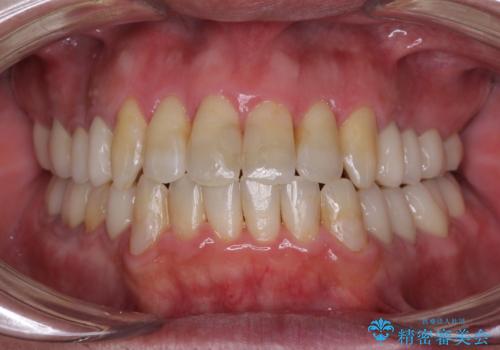

先天欠損のある歯列 インビザライン矯正

- 上顎前歯の突出感を気にして来院された患者様です。

下顎前歯2本が先天欠損しており、上顎歯列に対して、下顎歯列がアンバランスに小さい状況でした。

左右上顎側切歯2本が矮小歯であるため、上顎の抜歯ではなく、IPR(歯と歯の間を削る)と歯列全体の後方移動によってバランスを整えることとしました。

目立ちにくい装置を希望されたため、インビザラインにて治療を行うこととしました。

歯列のバランスが悪く、インビザライン矯正特有の奥歯の噛みにくさがなかなか改善されず、治療期間が長期化してしまいました。